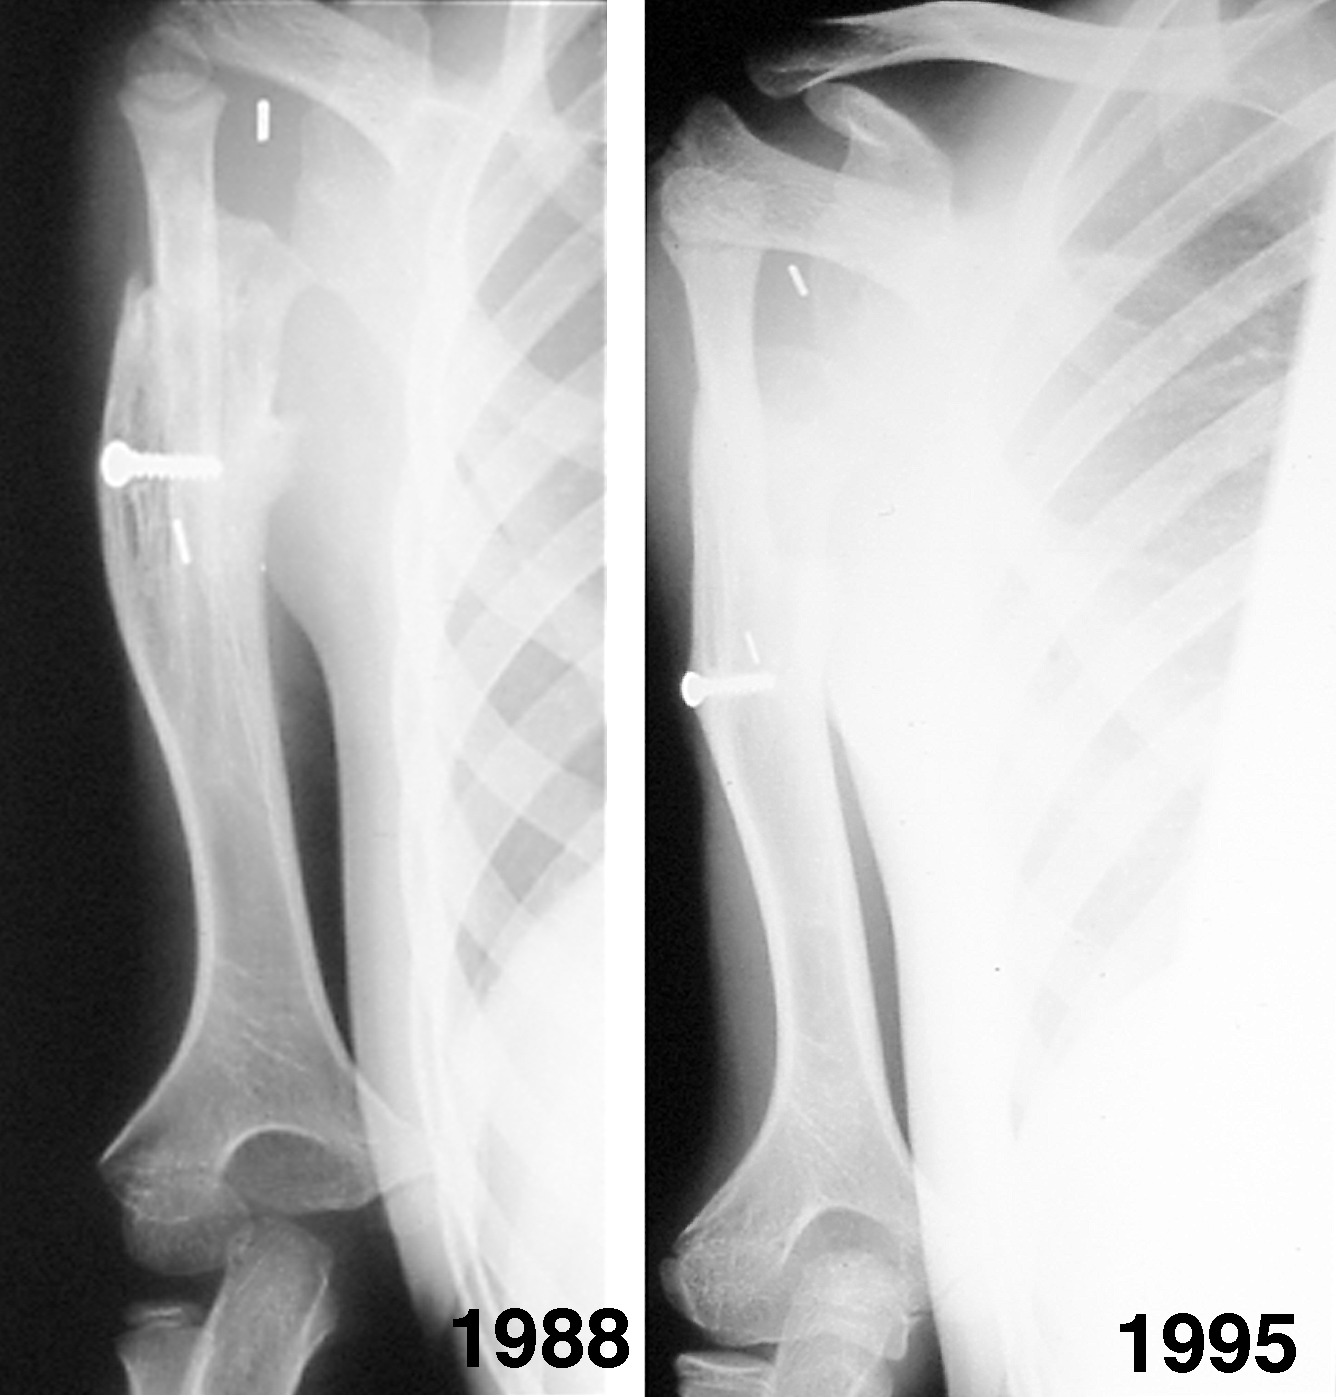

Another transplant was performed in a five-year-old boy (Case 4). He presented with an absent growth plate at the upper end of his right humerus as a result of neonatal septicaemia, which caused him to have a very short arm (Figure 20A). Similar to the previous patient, the upper end of the fibula growth plate was transferred on the anterior tibial vessels. The head of the fibula was secured in the shoulder joint by using the biceps tendon and sutured around the base of the coracoid process of the scapula. A small skin flap design was used to monitor the anastomoses (Figure 20B and C).

The bone transplant united to the humerus and fibula growth occurred at a rate similar to the epiphyseal transfer in the previous patient (see Figure 18). He was lost to follow up for many years and was seen again at age 15, when it was found that the upper end of the fibula had dislocated anteriorly and superiorly (Figure 21 and Figure 22). Despite this deformity that understated the true growth in the transplant, he had pain-free movement of the shoulder and was a very active surfboarder.